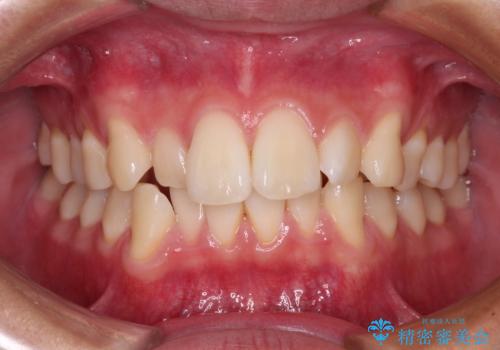

- 口を閉じたときに飛び出してしまう上顎前歯を気にして来院された患者様です。

下顎はデコボコが気になっていたため、上下左右第一小臼歯4本を抜去して、ワイヤー装置にて口元の突出感を改善するよう矯正治療を行うこととしました。

下唇に前歯が当たって跡が残ってしまう状態でしたが、スッキリとした口元に仕上げることができました。